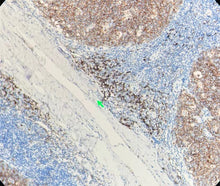

Contrôle positif : Tissu amygdalien